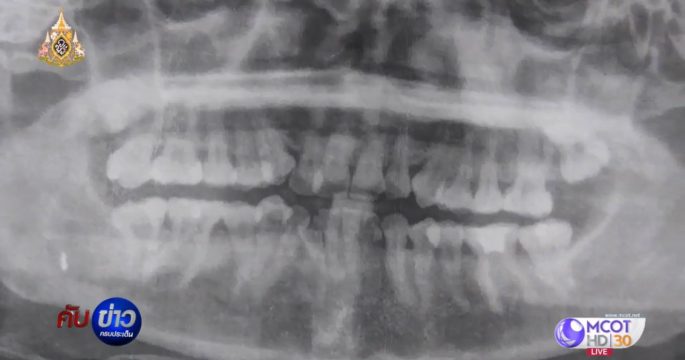

ผ่านพ้นไปด้วยดีกับเคสการผ่าตัดนำหัวกรอฟันที่ฝังในเหงือกคนไข้สร้างความทรมานนานกว่า 5 ปี มาเปิดไทม์ไลน์ย้อนดูเหตุการณ์ตั้งเเต่เริ่มกัน!

ความคืบหน้า กรณีหมอลืมหัวกรอฟันในเหงือกนางกฤติกานาน 5 ปี ล่าสุดทันตแพทย์ มหาวิทยาลัยขอนแก่น ผ่าออกแล้ว

หญิงวัย 33 ปี ผ่าฟันคุดออก แต่ทันตแพทย์ลืมหัวหรอฟันติดอยู่ในเหงือกนาน 5 ปี จนลิ้นรับรสไม่ได้ วอนหน่วยงานที่เกี่ยวข้องช่วยเหลือรับผิดชอบ